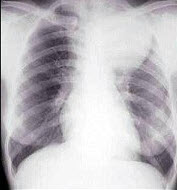

女,25岁,胸背痛半月余,胸片如图,最可能的诊断为()

A.左上肺不张

B.左上肺炎

C.纵隔肿瘤

D.左上肺癌

E.左上肺炎性假瘤